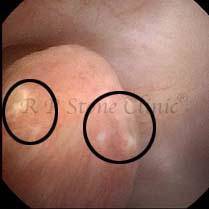

Kidney stone is a solid mass of CRYSTALS. It is the process of crystallization which initiates the formation of kidney stones. This happens in nephrons or units of kidney. Once a small crystal is formed, it can both grow & unite with other crystals leading to the formation of small concretion which eventually forms a stone. Once these large crystals detach from the collecting ducts, the process of stone formation starts in the renal collecting system. A recurrent kidney stone former is advised to know a little bit about something known as Randall’s plaque. Alexander Randall discovered plaques on the renal papillae eight decades back based on examination of 1154 pairs of autopsied Kidneys. He described these renal papillary lesions as cream colored or milk patch areas composed of calcium phosphate & calcium carbonate. These plaques could act as NIDUS for formation of KIDNEY STONE. Calcium Oxalate stone can form on this nidus & then detaches from this plaque to become a free floating stone in the collecting system of kidney

These images are taken as snap shots from the video recording of RIRS Surgery done at our hospital. These are Randall’s Plaques seen with Digital FLEX XC & Digital FLEX XC S. The cream or whitish patches are seen on the tips of RENAL PAPILLAE as seen in images below.

Randall’s Plaques may lead to the formation of Stones.

Those kidney stone patients who have Randall’s Plaques in their kidneys are more likely to form stones again (Recurrent Stones).

Stone Patients in whom Randall’s Plaques are detected at the time of RIRS Surgery should undergo regular ultrasound examination for early detection of stones.

Patients of Stones with Randall’s Plaques in their Kidneys should drink plenty of fluids in addition to Orange Juice & Lemonade.